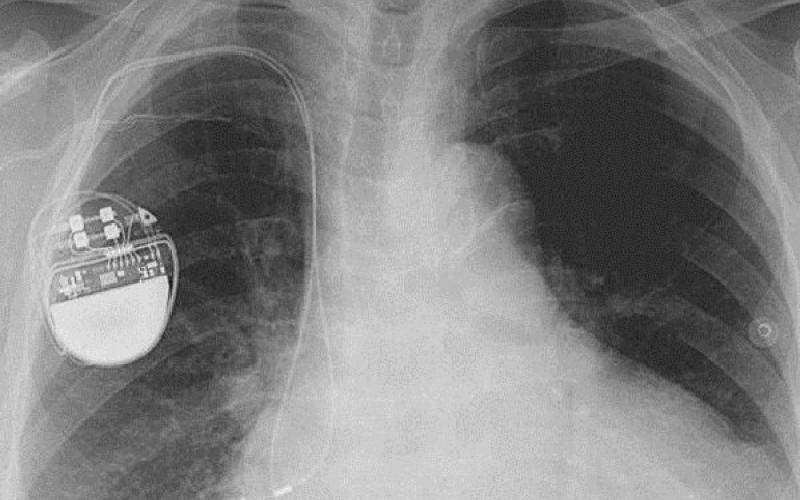

کارشناسان امنیتی هشدار می دهند که هکرها می توانند با نفوذ به دستگاه های تنظیم ضربان قلب که در داخل بدن انسان کار گذاشته می شود، زندگی این بیماران را به خطر بیندازند.

به گزارش سیتنا به نقل از گیزمودو، بسیاری از تجهیزات پزشکی مبتنی بر فناوری اطلاعات مانند پمپ های تزریق انسولین و دستگاه های تنظیم کننده ضربان قلب از آسیب پذیری هایی برخوردار هستند که دستکاری آنها برای هکرها را ممکن می کند.

محققان شرکت امنیتی وایت اسکوپ می گویند دستگاه های تنظیم ضربان قلب ۴ شرکت مشهور سازنده این نوع تجهیزات و همین طور سیستم های مورد استفاده برای کنترل و بررسی عملکرد دستگاه های یاد شده در مجموع دارای ۸۰۰۰ آسیب پذیری مختلف هستند و این تعداد بی سابقه از اشکالات بسیار نگران کننده است.

کارشناسان وایت اسکوپ می گویند سیستم های نرم افزاری تولیدات هر چهار شرکت قدیمی و به روز نشده بوده و اطلاعات خصوصی مربوط به هر بیمار به طور رمزگذاری نشده بر روی آنها ذخیره می شود. لذا در زمان اتصال آنها به سیستم های نظارتی بدون نیاز به ورود کلمه عبور می توان به این اطلاعات دسترسی پیدا کرد.

این اولین بار نیست که هشدارهایی در مورد امنیت پایین تجهیزات حساس پزشکی منتشر می شود. در سال ۲۰۱۳ هم هکری به نام بارنابی جک از فاصله ۱۵ متری توانسته بود شوکی مرگبار به یک دستگاه کنترل ضربان قلب وارد کند، اما شرکت های سازنده این نوع تجهیزات هشدارهای یاد شده را جدی نمی گیرند.